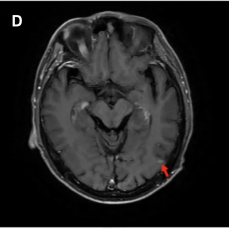

头颅增强MRI及DWI:左侧额叶见一结节样强化灶,考虑转移瘤(图2)。

图2 初诊时颅脑病灶(红色箭头指向病灶)[1]

头颅增强MRI及DWI:左侧额叶原有病灶较前增大(图4C),左侧颞枕叶交界区见新发病灶(图4D)。

图4 右肺病灶、左侧腋窝淋巴结及颅脑病灶复查结果(红色箭头指向病灶)[1]